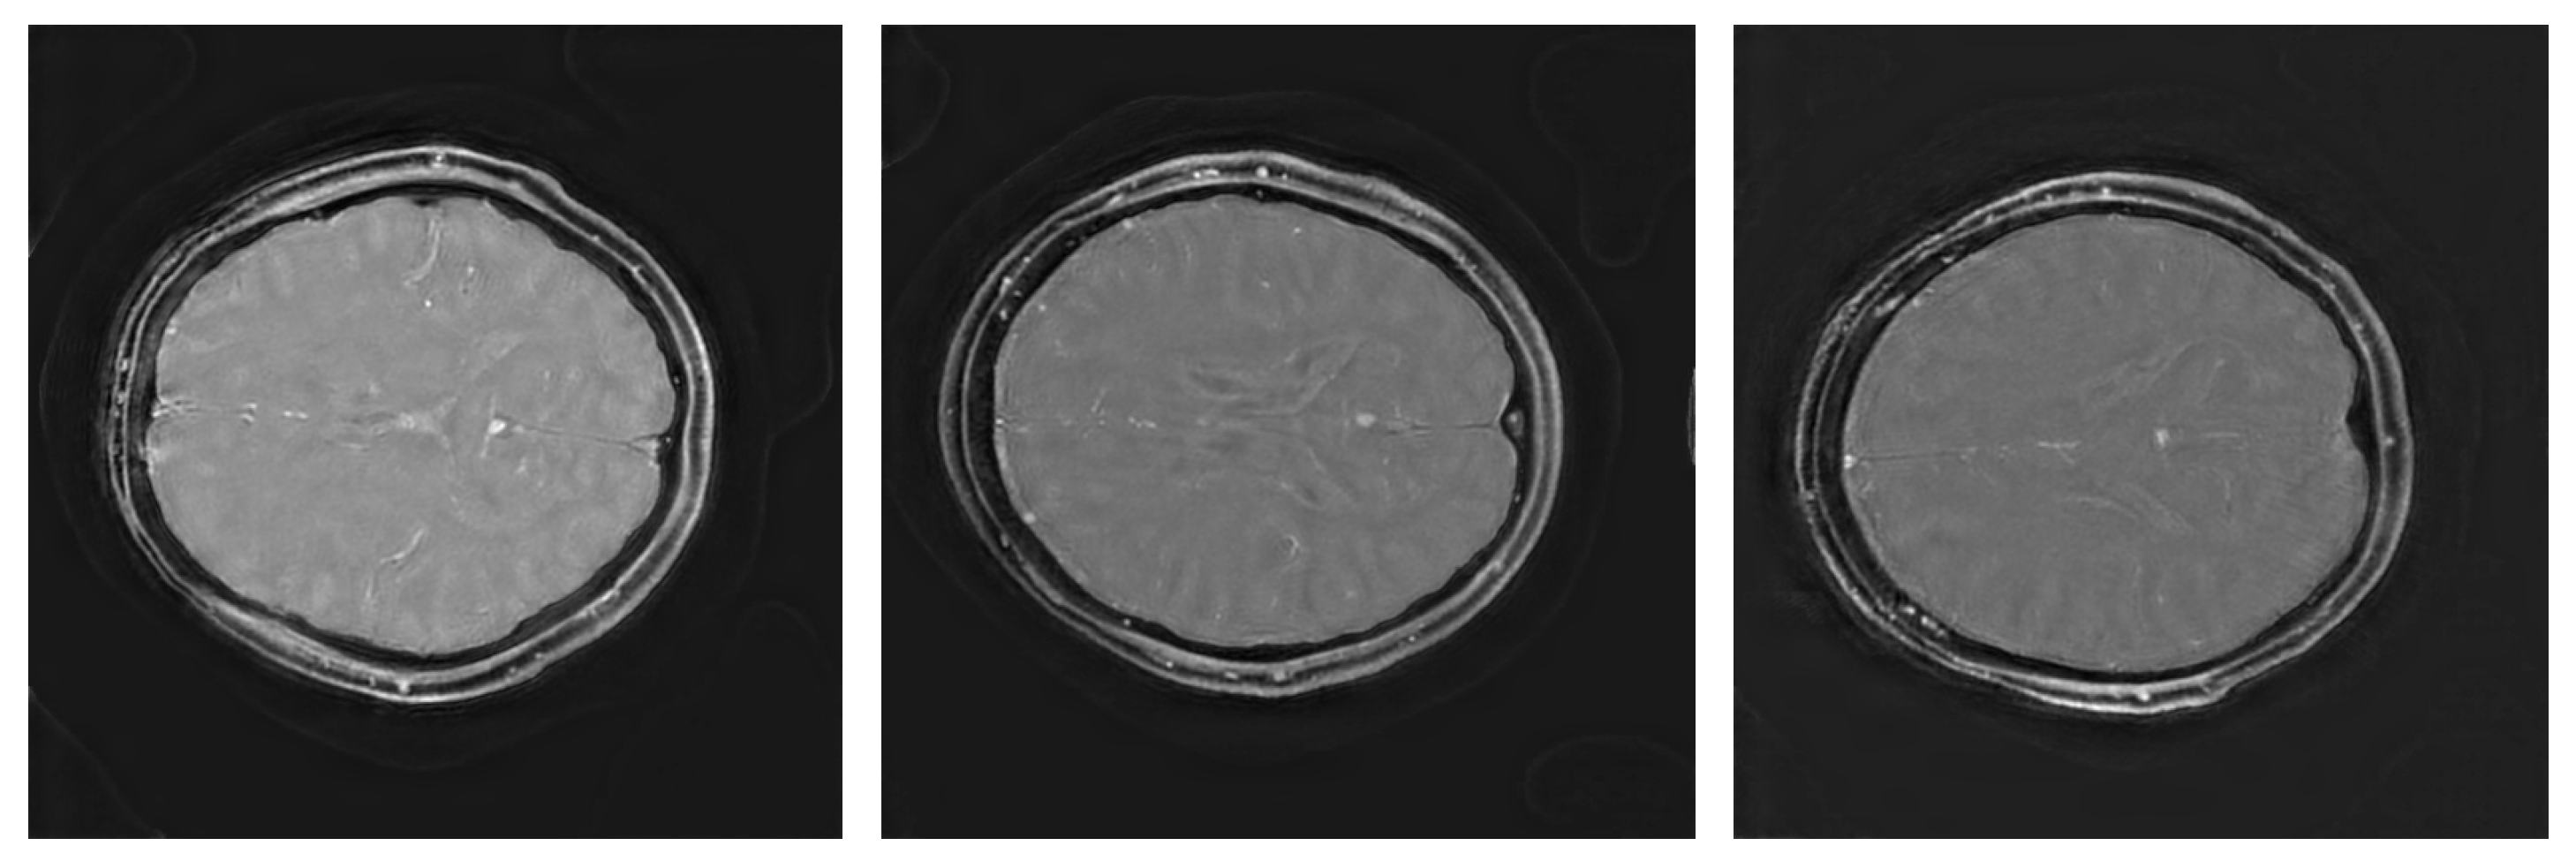

Figure 3 illustrates sample triply augmented ViT results from the network. Figure 4 shows the same image reconstructed by VarNet, MoDL, and the ViT pipeline; the final subfigure shows the amplified difference between the PICS and the ViT reconstructions.

Figure 3. Triply augmented ViT reconstructions for all three subjects